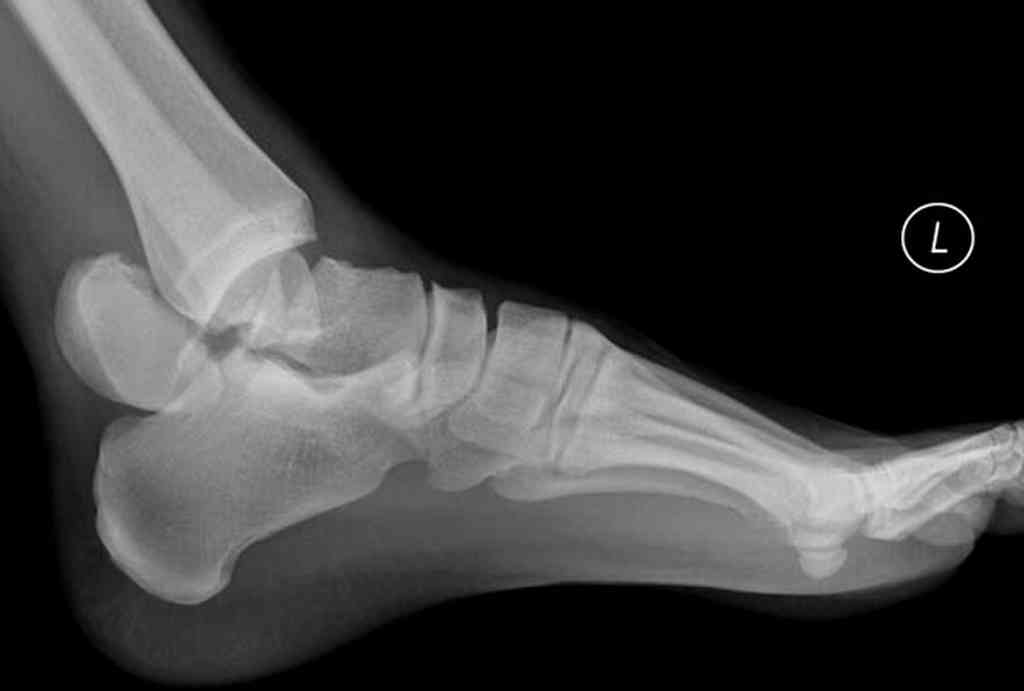

Здесь на фото примеры:

Переломовывих тарана с повреждением медиальной стороны. Через 4 часа после поступления проведена репозиция и фиксация тарана после Irrigation&Debridment. Частичное несращение медиальной лодыжки не беспокоит, вернулся к активному образу жизни. Полная нагрузка разрешена через 11 недель. Финальные снимки через 11 месяцев.